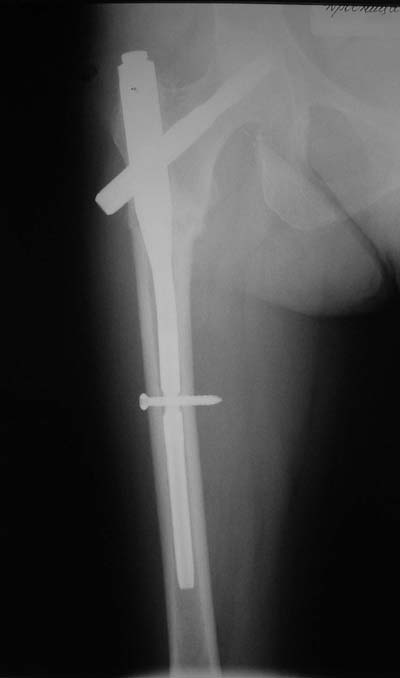

Присоединяюсь. Хотя посмотреть бы вторую проекцию.

И по фасу - шеечый винт можно бы и подлиннее.

АС> Дистальное блокирование провели правильно: статическое.

Нижний винт тут, насколько я понимаю, не особо нужен, поскольку проксимальный винт проходит через дистальный отломок.

Да наутро после операции. Все проксимальные фиксаторы рассчитаны на немедленную нагрузку, но при непременном условии - правильном расположении шеечного винта в шейке и головке.

Да? Качество рентгенограмм конечно неочень, но ведь это нестабильный перелом 31.А2.2, не так ли?